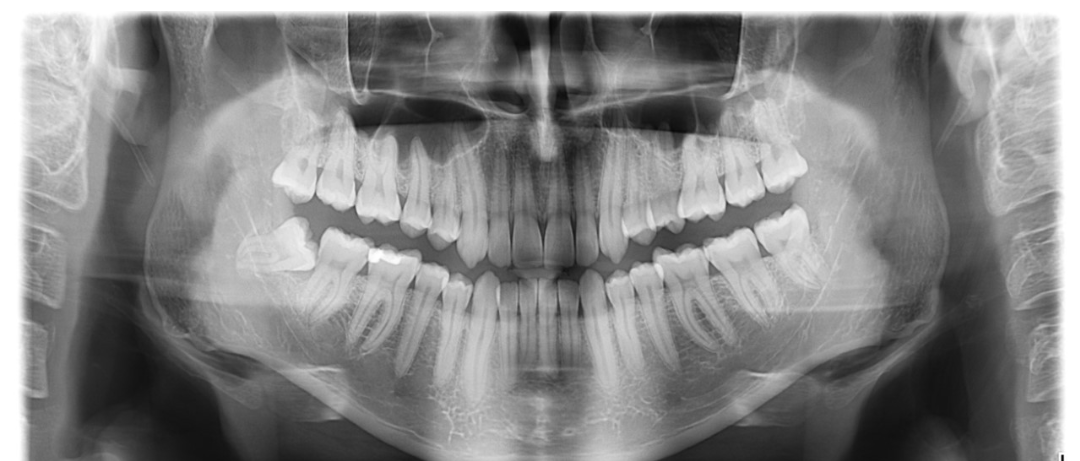

Η πανοραμική μου,κάτω αριστερά ο φρονιμοτης

Αχ και εμένα αυτός είναι.. εσύ πόσο καιρό το είχες ημιεγκλειστο πριν το βγάλεις;View attachment 114558

Και εμένα κάπως έτσι ήταν αλλά λίγο πιο οριζόντιοι. Εγώ τους είχα αρκετά χρόνια έτσι, δεν μου προκάλεσαν θέμα πέρα από pockets 10+ χιλιοστών και τους έβγαλα για αυτόν τον λόγο γιατί θα πάθαινα περιοδοντίτιδα. Αν θυμάμαι καλά πήρε 45 λεπτά να βγάλει 2 έγκλειστους και 2 κανονικούς. Δεν είχα πρήξιμο γιατί μου έδωσε dexamethasoneΑχ και εμένα αυτός είναι.. εσύ πόσο καιρό το είχες ημιεγκλειστο πριν το βγάλεις;

Εγώ έναν έγκλειστο έχω, αυτόν. Απ' ότι βλέπω τα άλλα έχουν βγει κανονικά..Και εμένα κάπως έτσι ήταν αλλά λίγο πιο οριζόντιοι. Εγώ τους είχα αρκετά χρόνια έτσι, δεν μου προκάλεσαν θέμα πέρα από pockets 10+ χιλιοστών και τους έβγαλα για αυτόν τον λόγο γιατί θα πάθαινα περιοδοντίτιδα. Αν θυμάμαι καλά πήρε 45 λεπτά να βγάλει 2 έγκλειστους και 2 κανονικούς. Δεν είχα πρήξιμο γιατί μου έδωσε dexamethasone